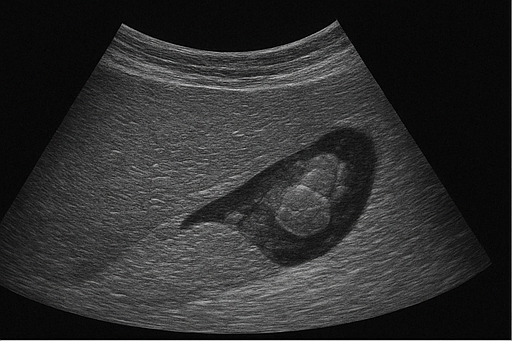

- 담석: 담낭이나 담관에 생긴 돌로, 초음파에서 밝은 음영과 그림자로 나타납니다.

- 신장 결석: 신장에 생긴 돌로, 초음파에서 밝은 음영과 그림자로 나타납니다.